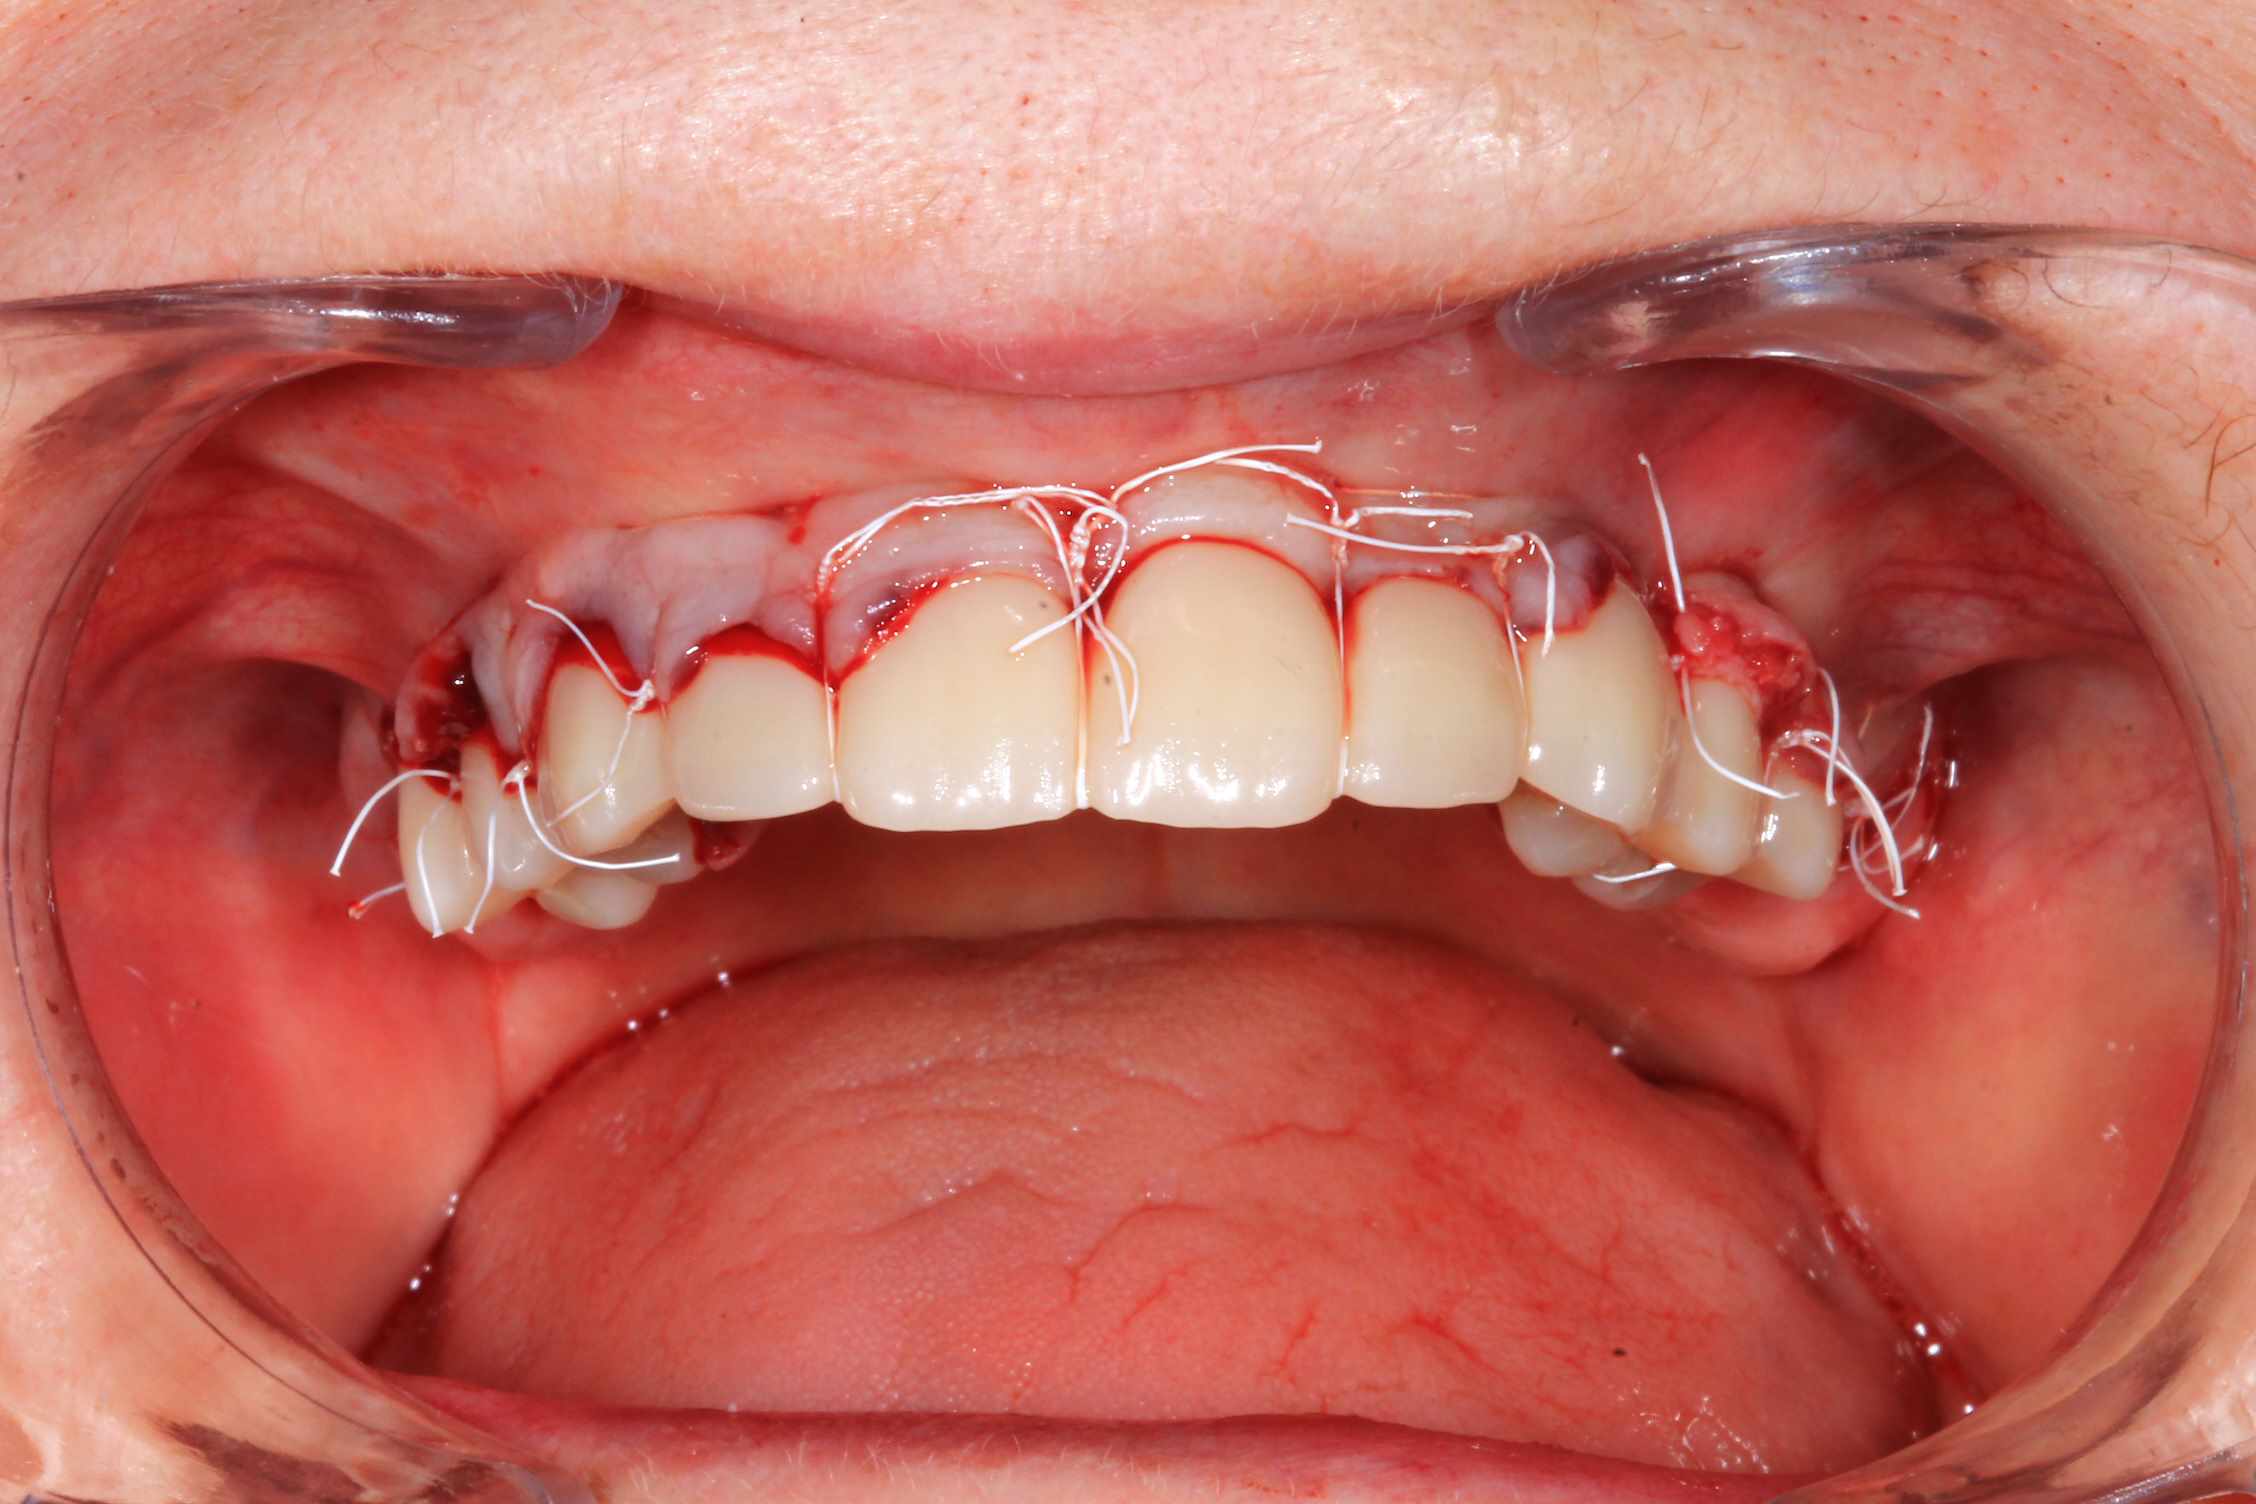

Cas 5 : extraction et all on 4. en bas , pas du tout d'os : décision de bridge complet avec une extension de chaque coté.

Modélisation : labo lio. Design et impression du guide : Teeth projet. Bridge full zircone katana myio rosenscrew en mise en charge instantanée , labo LIO.

Guide a etage avec fixtion de l'etage clavette par rapport aux dents avant extraction. Extraction.

Fixation du guide de forage sur le guide clavette. pose des implants, des piliers ( tres classique ), et du bridge zircone rosenscrew. Stickybone The Graft, sutures suspendues et résultat post op et un mois.